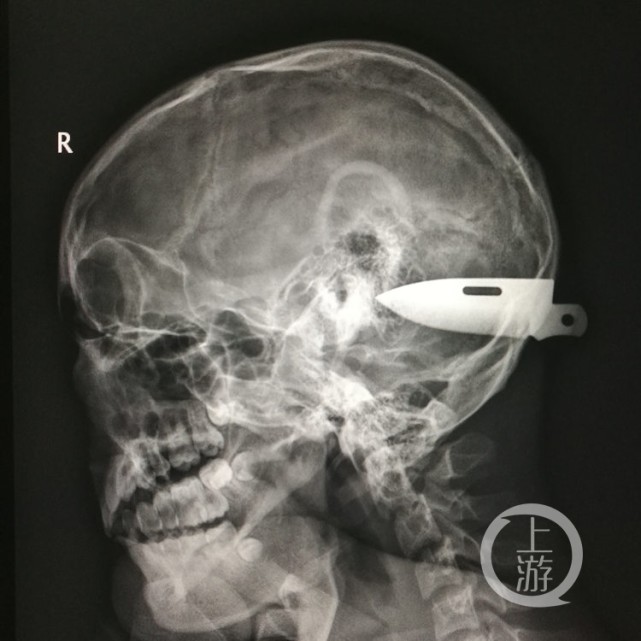

8厘米刀片插入男子脑中刺穿小脑 医生半夜“拔刀”

CT和取出的刀片。医院供图

飞刀长达8厘米 横贯小脑“脑花”

刀片取出后,测量长达8厘米。这8厘米的刀片,穿过后脑勺的颅骨,横贯小脑的“脑花”。刀尖的破口离脑部乙状窦只有2毫米,刀刃破口离横窦5毫米,“这两个窦是颅内最重要的静脉,几乎颅内所有的血液都通过它们回流到心脏。”一旦它们被刀刺断,就会导致不可控制的大出血,后果将不堪设想。